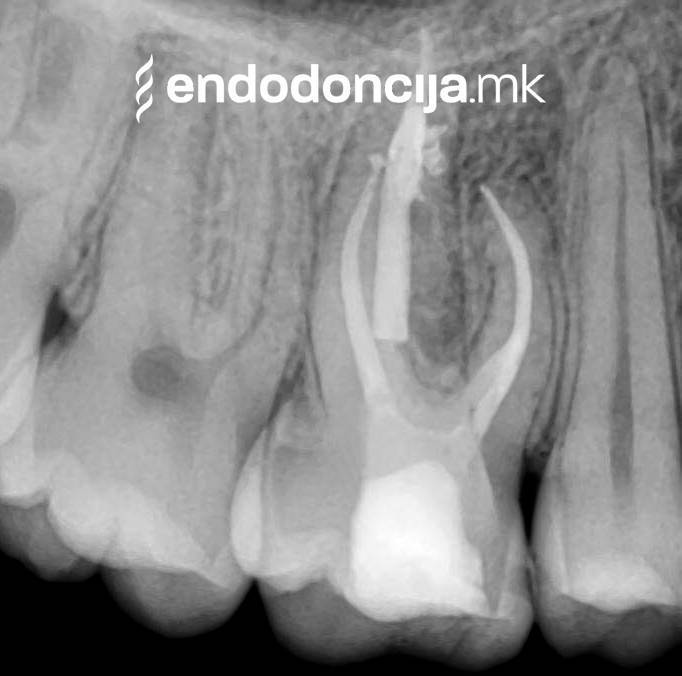

Κατά τη διάρκεια της επεξεργασίας του ριζικού σωλήνα, τα λεπτά όργανα ενδέχεται να σπάσουν. Αυτό μπορεί να αποτελέσει εμπόδιο για την πλήρη προετοιμασία και τον καθαρισμό του ριζικού σωλήνα. Με μια μικροσκοπική επεξεργασία του ριζικού σωλήνα μπορεί να είναι δυνατή η απομάκρυνσή τους υπό ορισμένες συνθήκες, χωρίς να καταστρέφεται η ουσία των δοντιών.

Με τη σωστή θεραπεία, όχι μόνο οι οξείες φλεγμονές αλλά και οι χρόνιες μπορούν επίσης να αντιμετωπιστούν με επιτυχία. Αυτά μπορεί να προκαλέσουν πόνο ή μερικές φορές ακόμη και εντελώς χωρίς συμπτώματα. Η έγκαιρη ανίχνευση και εξάλειψη τέτοιων φλεγμονών είναι ζωτικής σημασίας για τη μακροχρόνια συντήρηση των δοντιών.

Σε περίπτωση ανανέωσης της θεραπείας του ριζικού καναλιού (αναθεώρηση) παλιά γεμίσματα ρίζας που δεν ήταν επιτυχημένα και ως εκ τούτου ήταν η αιτία φλεγμονών και πόνου, μπορούν να αφαιρεθούν και να ανανεωθούν εξειδικευμένα. Αυτή η θεραπεία εξαλείφει τις φλεγμονές στην περιοχή της ρίζας και καθίσταται δυνατή η πλήρης ανάρρωση.